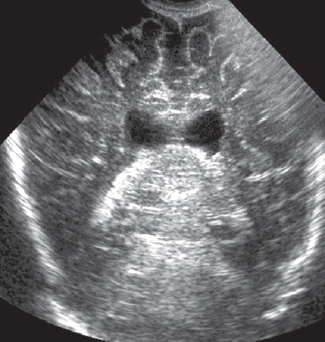

Рис. 1. Магнитно-резонансная томограмма головного мозга пациента, фронтальный срез: а— на уровне базальных ганглиев; b— с визуализацией гиппокампов / Fig. 1. Patients brain, magnetic resonance imaging, front: a – T1 hyperintensity symmetric of basal nuclei; b–hippocampus, cortex and brain hypotrophy are evidence

На 27-й день жизни выполнена МРТ головного мозга, диагностирована гипоксически-ишемическая энцефалопатия с двухсторонним поражением базальных ядер, ножек мозга, прецентральной извилины и гиппокампов. Кроме того, выявлена смешанная гидроцефалия по заместительному типу (рис. 1, 2). Визуализируется симметричное усиление МР-сигнала в области базальных ганглиев (рис. 1, а), гиппокампов (рис. 1, b), также определяется значительное расширение субарахноидальных пространств, преимущественно над лобными, височными долями больших полушарий с расширением сильвиевой щели, расширение борозд и истончение коры больших полушарий (наружная гидроцефалия по заместительному типу), расширение передних отделов боковых желудочков.